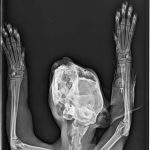

A sokktalanítás után, bódításban tudták csak megvizsgálni, borzasztóan félt és hatalmas fájdalmai voltak. Sajnos a fájdalom oka a hátsó lába iszonyatos sérülése volt. A térde szilánkosra törve és a lágy részek rendkívül súlyosan roncsolódtak. Az első orvosi vélemények szerint 75% az esélye, hogy ezt a lábat nem tudják megmenteni már, tegnap este azután az ortopéd orvos is megvizsgálta és az ő véleménye szerint sem menthető a lábikó. A mai nap stabilizálták az állapotát, erősítik kicsit és holnap sor kerül a műtétre. Az első lábacskája szintén zúzódott, nagyon be van dagadva, itt azonban megvan a remény a teljes gyógyulásra.